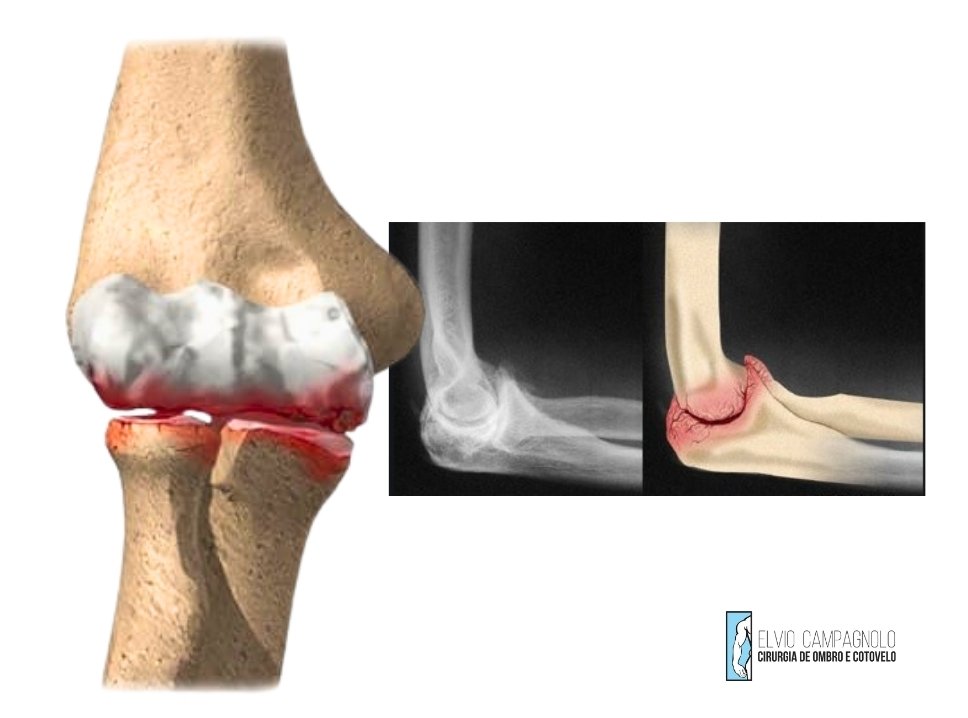

A artrose do cotovelo é uma condição degenerativa em que há desgaste da cartilagem articular, resultando em atrito entre os ossos e inflamação. Pode surgir após traumas, fraturas, sobrecarga repetitiva ou como parte do envelhecimento natural.

Os sintomas incluem dor progressiva, rigidez articular, limitação de movimento e estalidos. Em casos avançados, o paciente pode apresentar travamentos e perda de força no braço.

O tratamento é inicialmente clínico, com fisioterapia, fortalecimento muscular e controle da inflamação por meio de medicamentos ou infiltrações guiadas por ultrassom. A viscossuplementação com ácido hialurônico e as terapias regenerativas podem oferecer melhora funcional importante. Em casos mais graves, com limitação significativa, pode ser indicada artroscopia para limpeza articular ou, em situações avançadas, prótese de cotovelo.